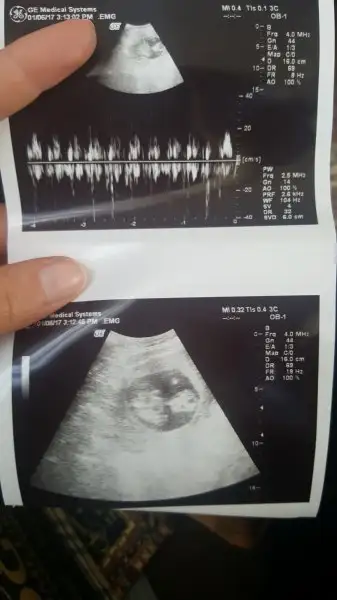

Hanımlar bişey sorcam, bugün kontrole gittim doktor bebek iyi sorun yok dedi, ayakta fazla kalmıyorsundur heralde dedi ben biraz huylandım öyle sorunca. Eve gelince de ultrason görüntülerinde bebeğin üstünde bişey olduğunu farkettim böyle bişey gören var mı ultrasonda? Moralim bozuldu :/

Hanımlar bişey sorcam, bugün kontrole gittim doktor bebek iyi sorun yok dedi, ayakta fazla kalmıyorsundur heralde dedi ben biraz huylandım öyle sorunca. Eve gelince de ultrason görüntülerinde bebeğin üstünde bişey olduğunu farkettim böyle bişey gören var mı ultrasonda? Moralim bozuldu :/Eki Görüntüle 2003183 Eki Görüntüle 2003184

Canım sanki plesentaya benziyor o bebeğin üstündeki şey yani bebeğin eşi. Normalde ultrason fotoğrafında görünür mu bilmem ama doktorlar ultrasonda gördüklerine göre fotoğrafta da görülebilir demekki. Koru bişey olsa doktorlar kesinlikle gizlemiyorlar bu konuda. Ayrıca ayakta kalma demesinin bununla bir ilgisi yok ben de öğretmenim doktorum Fazla Ayakta kalıyorsun tedbir amaçlı progeston verebilirim demişti ben onun yerine rapor aldım 10 gün şimdi yine işe başladım ama genelde oturuyorum fazla dolanmiyorum. Çok ayakta durmanın riskleri var o yüzden doktorun sana uyarı anlamında demistir

Ne bileyim doktor acaba gözden mi kaçırdı diye korktum. İnternette de bu haftanın ultrason görüntülerine baktım hiçbirinde böyle bişey yok. Plasenta mı ayrıldı acaba diye korkuyorum

Yok canım plesenta ayrılmış olsa bunu gözden kaçırmasi mümkün değil doktorum ki ben o olayın son haftalarda olduğunu duymuştum allah korusun hiç bir zaman olmasın inşallah. Bence fotoğrafın açısından dolayı plesenta çok net çıkmış. Çünkü ben daha önceden ultrason fotoğraflarına bakarken internetten hep böyle görüyordum ok işaretiyle de plesenta yazıyordu üstünde hep